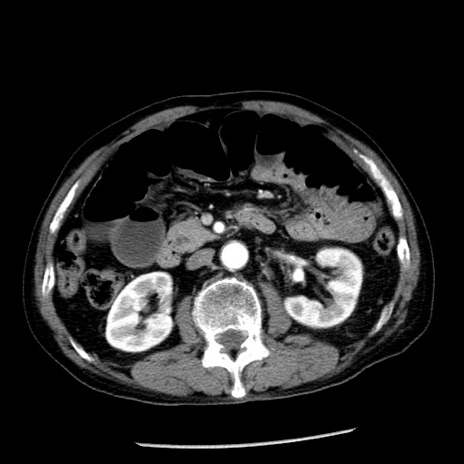

症例26(横断像)

【症例】80歳代男性

【主訴】嘔吐

【現病歴】昨晩2回嘔吐あり、今朝になっても嘔吐あり。来院。

【既往歴】胃潰瘍

【身体所見】意識清明、BT 37.6℃、BP 166/95mmHg、HR 100bpm、SpO2 97%、腹部:平坦・軟、腸蠕動音聴取良好、圧痛なし。

【データ】WBC 21900、CRP 1.46